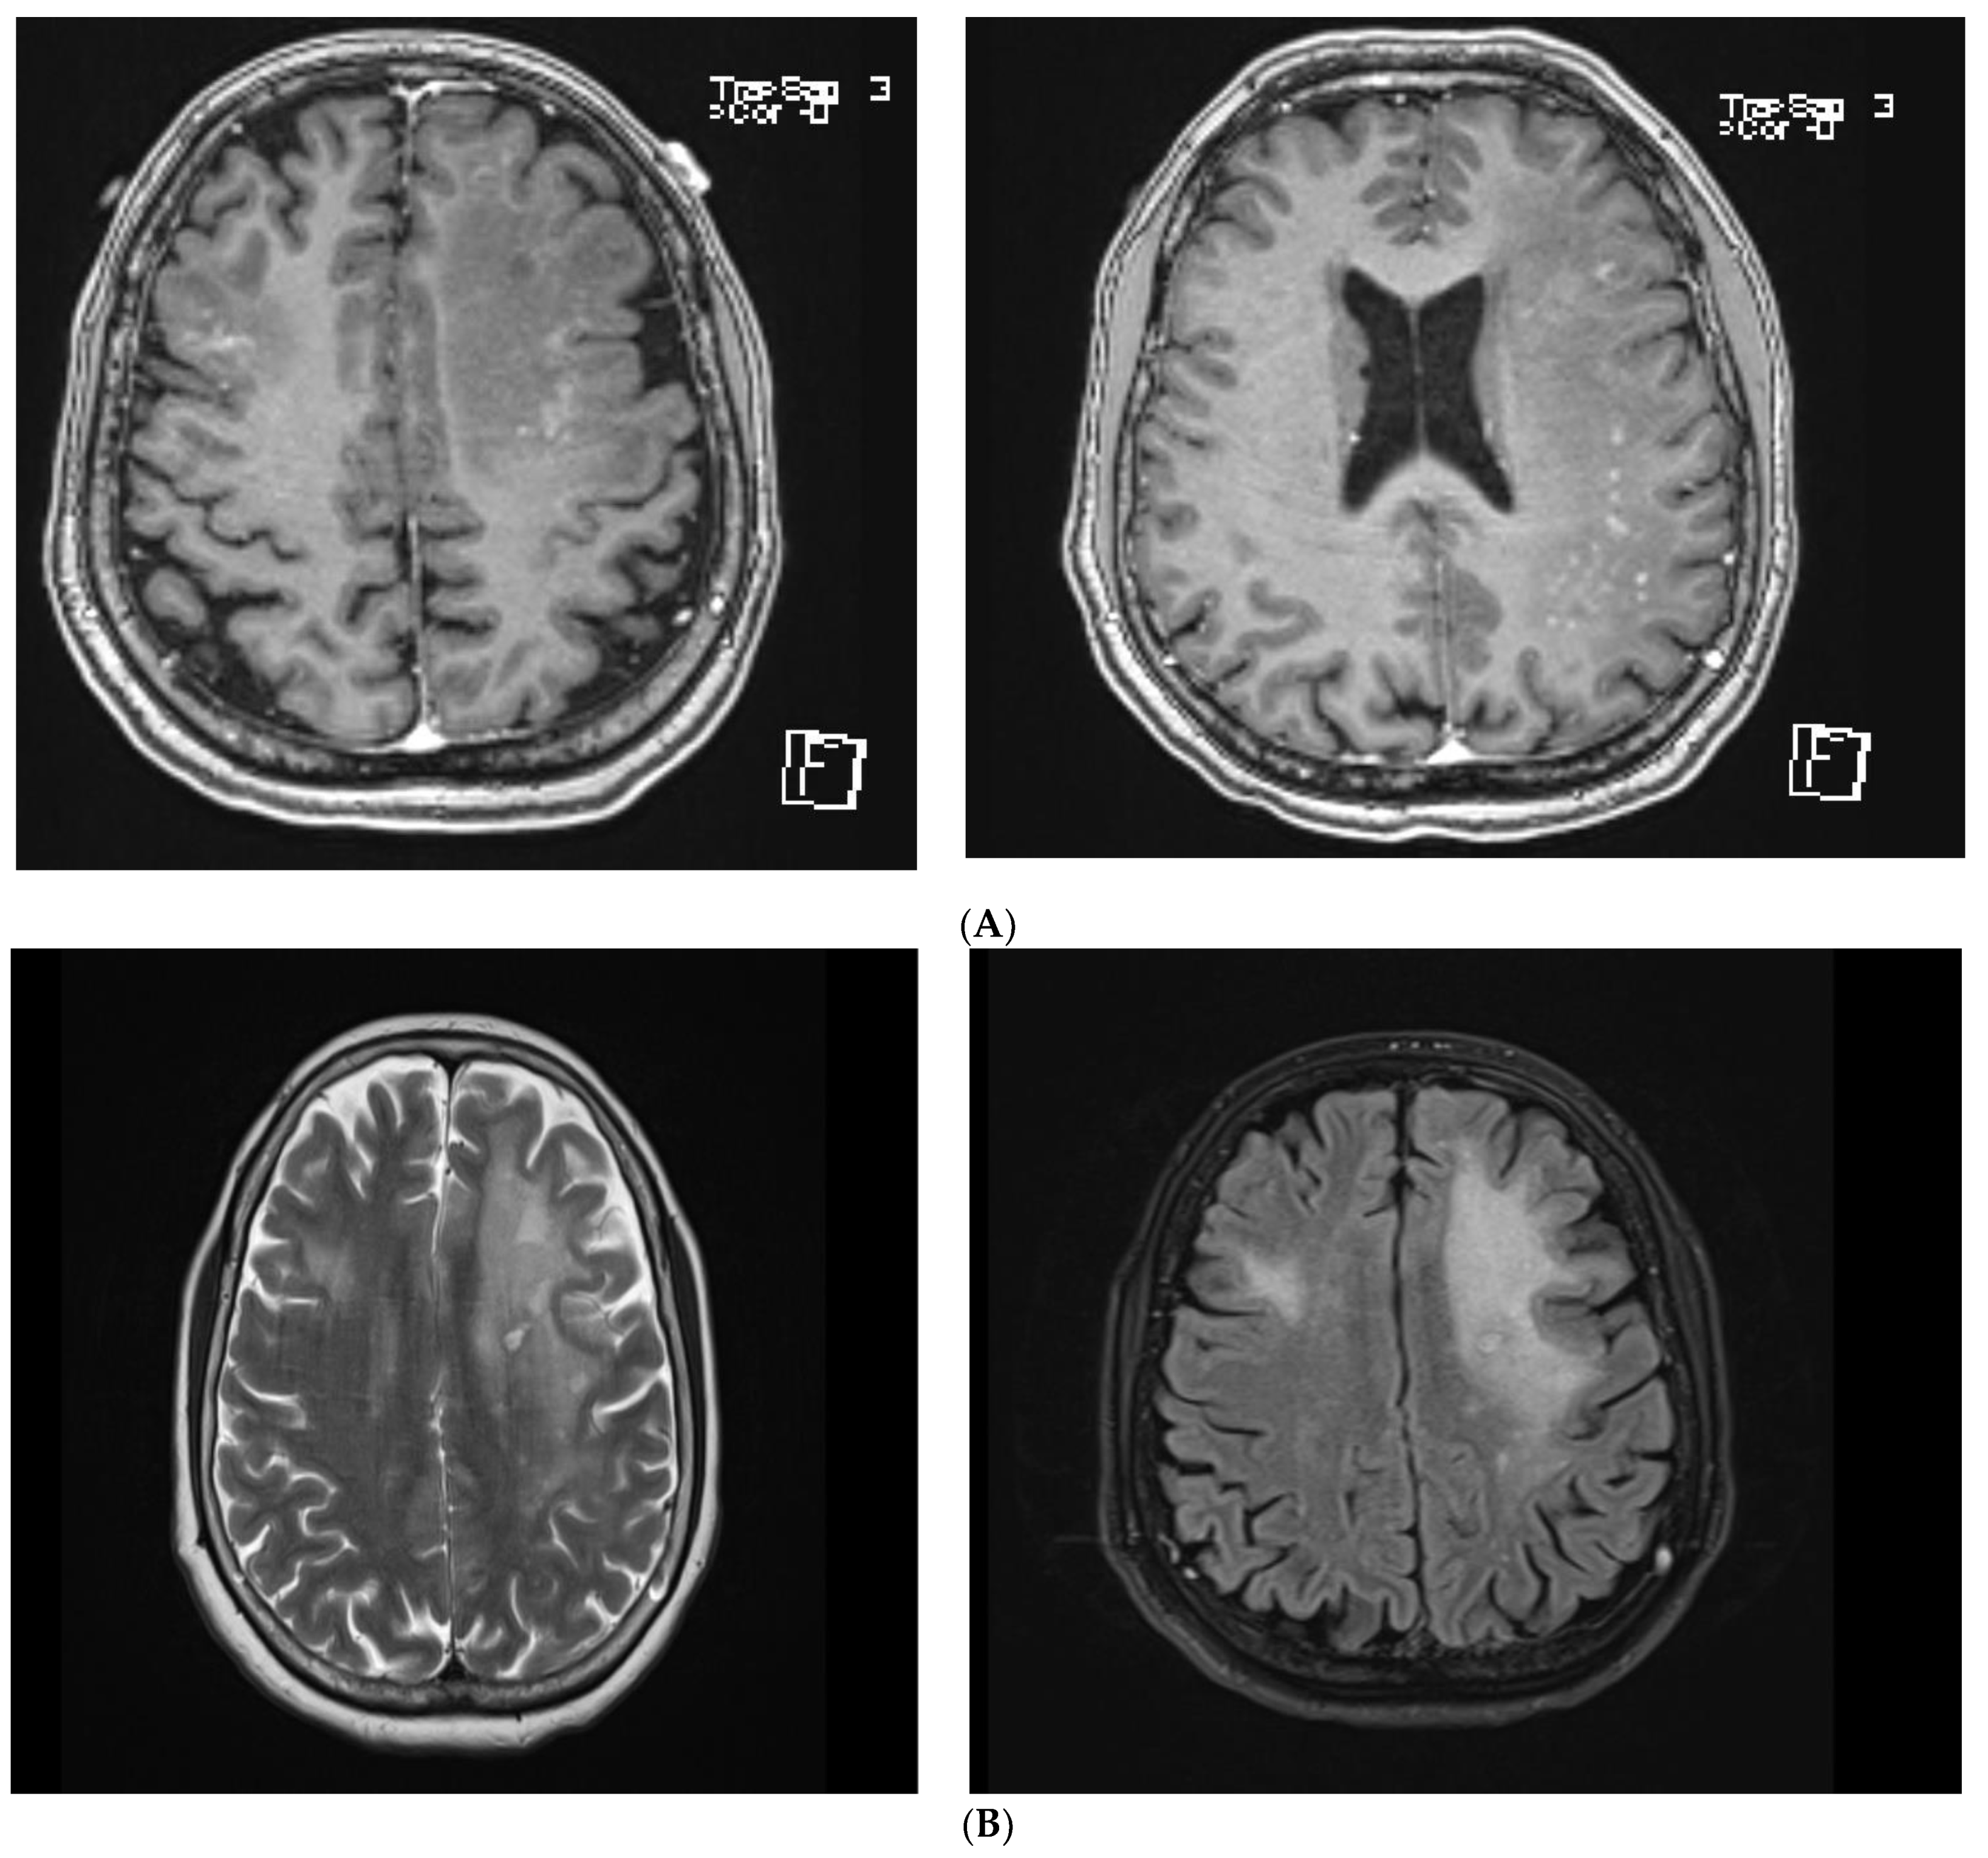

A Diagnostic Dilemma of White Matter Lesions and Cerebral Oedema without Identifiable Cause—A Neurological Conundrum

2. Case Report